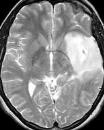

Machine learning has been widely adopted for medical image analysis in recent years given its promising performance in image segmentation and classification tasks. The success of machine learning, in particular supervised learning, depends on the availability of manually annotated datasets. For medical imaging applications, such annotated datasets are not easy to acquire, it takes a substantial amount of time and resource to curate an annotated medical image set. In this paper, we propose an efficient annotation framework for brain MR images that can suggest informative sample images for human experts to annotate. We evaluate the framework on two different brain image analysis tasks, namely brain tumour segmentation and whole brain segmentation. Experiments show that for brain tumour segmentation task on the BraTS 2019 dataset, training a segmentation model with only 7% suggestively annotated image samples can achieve a performance comparable to that of training on the full dataset. For whole brain segmentation on the MALC dataset, training with 42% suggestively annotated image samples can achieve a comparable performance to training on the full dataset. The proposed framework demonstrates a promising way to save manual annotation cost and improve data efficiency in medical imaging applications.

翻译:近年来,由于在图像分割和分类任务方面表现良好,医学图像分析广泛采用了机器学习。机器学习的成功,特别是监督学习的成功,取决于手动附加说明数据集的可用性。对于医疗成像应用来说,这种附加说明数据集不容易获得,需要大量的时间和资源来翻译附加说明的医学成像集。在本文件中,我们建议为大脑MR图像建立一个高效的注释框架,为人类专家提供信息性样图像,供人类专家作说明。我们评估了两种不同的大脑图像分析任务的框架,即脑肿瘤分割和整个大脑分割。实验显示,对于BRATS 2019数据集的脑肿瘤分割任务,培训一个只有7%的附加说明图像样本的分解模型,其性能与全数据集培训的性能相当。对于MALC数据集的整个大脑分割,用42%的附加说明性图像样本进行的培训,可以实现与全数据集培训的类似性能。拟议的框架展示了节省人工注解成本和提高医疗成像应用数据效率的有希望的方法。